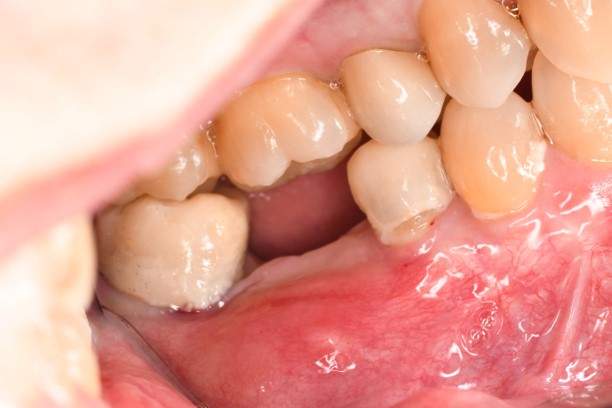

インプラント治療の症例4

口腔内写真

- Befor

- After

| 年齢 | 50代・男性 |

| 主訴 | 部位:左下6番7番 主訴:左下奥歯腫れて痛い。 |

| 治療内容 | 左下6番抜歯、左下6番7番骨造成、インプラント埋入 |

| 治療費 | 合計:1,232,000円 ・内訳 診断料:55,000円 サージカルガイド2本:66,000円 GBR:110,000円×2本 埋入料:165,000円×2本 静脈内鎮静麻酔:77,000円 2次OPE:22,000円×2本 仮歯:55,000円×2本 上部構造(フルジルコニア):165,000円×2本 (2023年1月現在) |

| 治療期間 | 約8ヶ月 |

| 治療方針 | 元々支台歯に負荷がかかりやすいとされている延長ブリッジを抜歯し、1本単体でしっかりかめるようにインプラントを2本埋入した。骨吸収も進んでいたため、※GBR法で骨造成を同時に行った。 治療と並行して、全顎的な歯周病治療も行い、今後は歯周病が進行しないよう、こまめにメンテナンスに通っていただく。 |

| 特記事項 | ※1 GBR・・・骨再生誘導法。骨の高さや厚みを人工骨や人工膜などを使用し再生する方法 |

| 担当者所見 | 6番は歯根分割された被せ物が7番の欠損部との延長ブリッジとされており、強い咬合と歯周病も相まって負荷がかかり動揺し、歯として機能しなくなったため、抜歯となった。 |